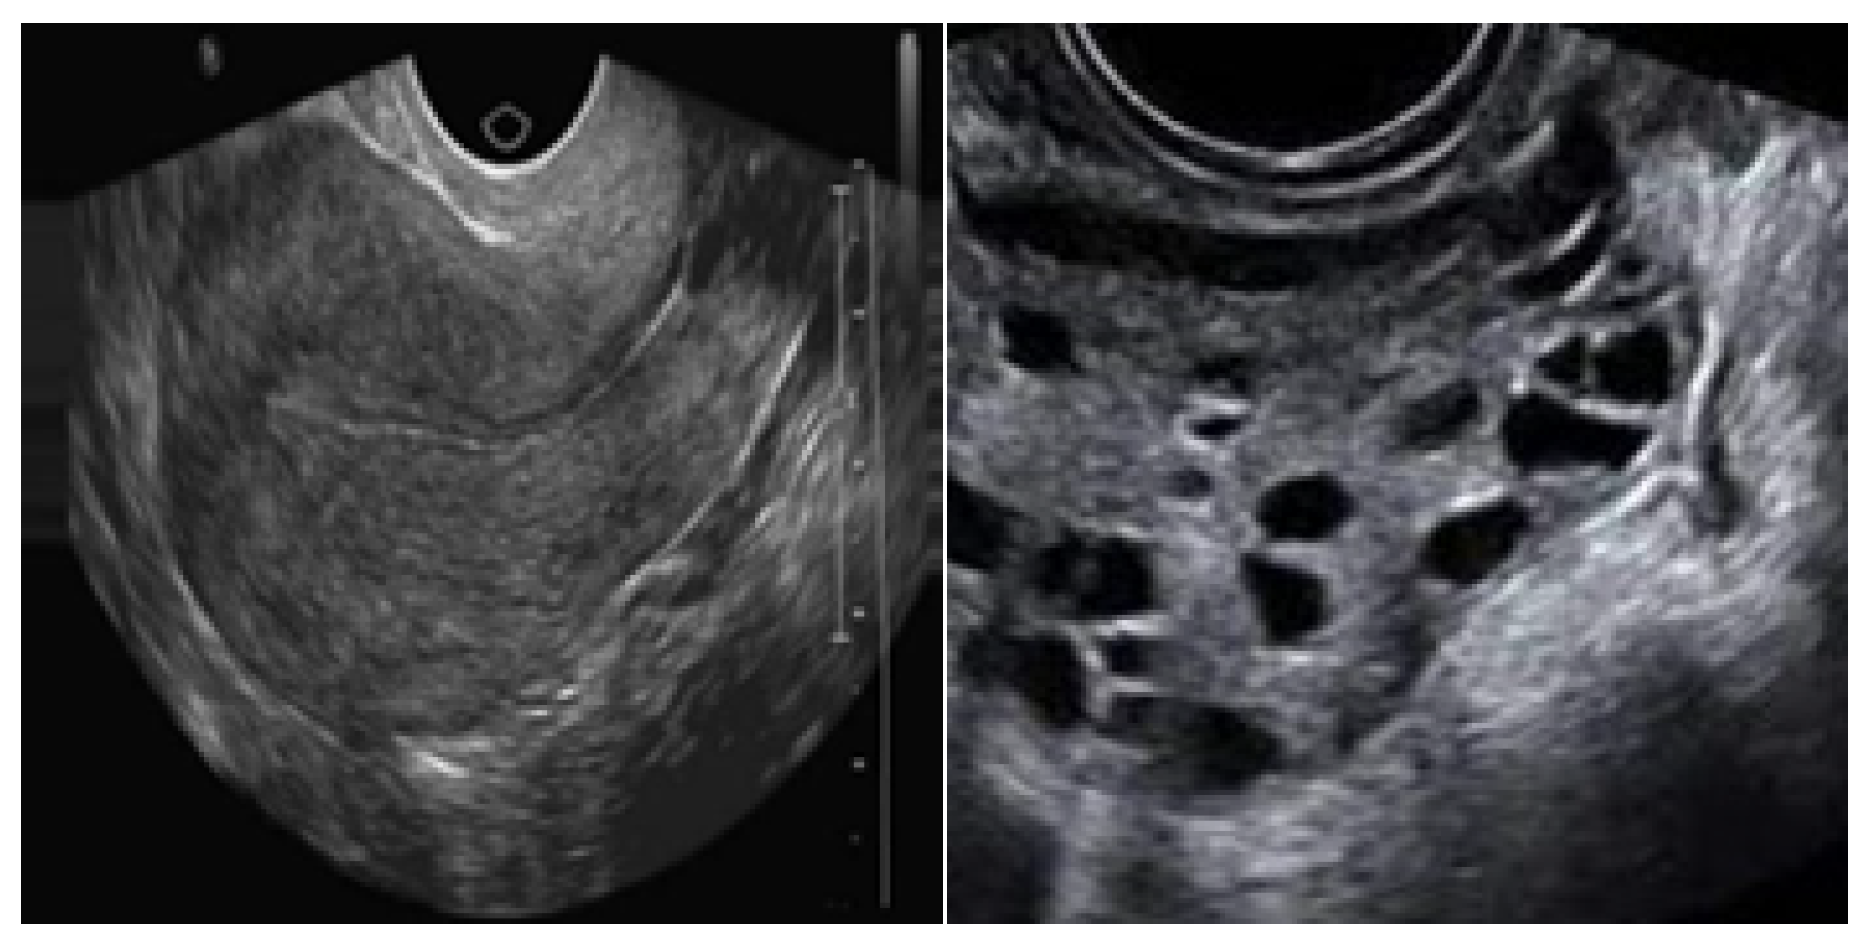

Denoising Degraded PCOS Ultrasound Images Using an Enhanced Denoising Diffusion Probabilistic Model

2. Materials and Methods